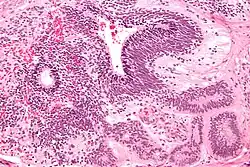

Yolk sac tumor

The ovarian yolk sac tumors, also known as endodermal sinus tumors, are accountable for approximately 15.5% of all OGCTs.[8] They have been observed in women particularly in their early ages, and rarely after 40 years of age.[9] The critical pathologic features are a smooth external surface and capsular tears due to their rapid rate of growth. A study consisting of 71 individual cases of ovarian yolk sac tumor provides evidence to the proliferation of the tumor. In one of the cases, the pelvic examination revealed normal activity until a 9 cm and 12 cm sized tumor was discovered 4 weeks later.[9] In another case, a 23 cm tumor was discovered in a pregnant woman who was monitored regularly and had normal findings until oophorectomy became essential.[9] Histologically, these tumors are characterized by mixed solid and cystic components.[1] The mixed solid components are characterized by a soft gray to yellow solid components accompanied with significant hemorrhage and necrosis. The cysts are approximately 2 cm in diameter and populated throughout the tissue which results in giving the neoplasm a ‘honeycombed appearance’.[1]